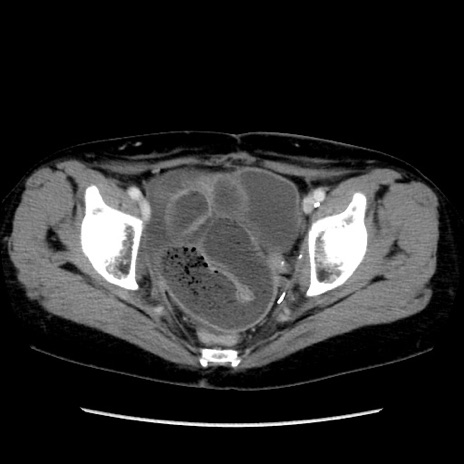

冠状断像

矢状断像